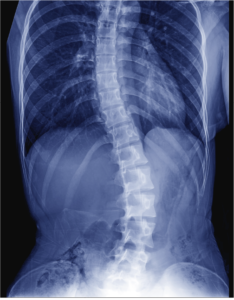

Scoliosis

Scoliosis is a condition characterized by abnormal curvature of the spine causing a deviation to one side. It causes a physical deformity making the spine…